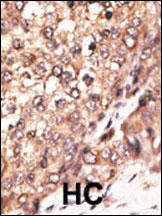

IHC 1/100-1/500 Human,Mouse,Rat

The Bmp7 (N-term) antibody is a targeted reagent designed to detect the N-terminal region of Bone Morphogenetic Protein 7 (BMP7), a member of the transforming growth factor-beta (TGF-β) superfamily. BMP7 plays critical roles in embryonic development, tissue repair, and homeostasis, particularly in bone and cartilage formation, kidney development, and neural patterning. It functions by binding to serine/threonine kinase receptors, activating SMAD signaling pathways to regulate gene expression. The antibody is typically raised in immunized hosts (e.g., rabbit, mouse) using synthetic peptides or recombinant proteins corresponding to the N-terminal epitope of BMP7. This design ensures specificity for full-length BMP7 or its isoforms containing the N-terminal domain, distinguishing it from other BMP family members. Validated applications include Western blotting, immunohistochemistry, and immunofluorescence, aiding in studies of BMP7 expression in developmental biology, organogenesis, and diseases like chronic kidney disease or cancer. Researchers use this antibody to explore BMP7's therapeutic potential or its dysregulation in pathological conditions. Proper controls, such as knockout tissues or blocking peptides, are recommended to confirm signal specificity.